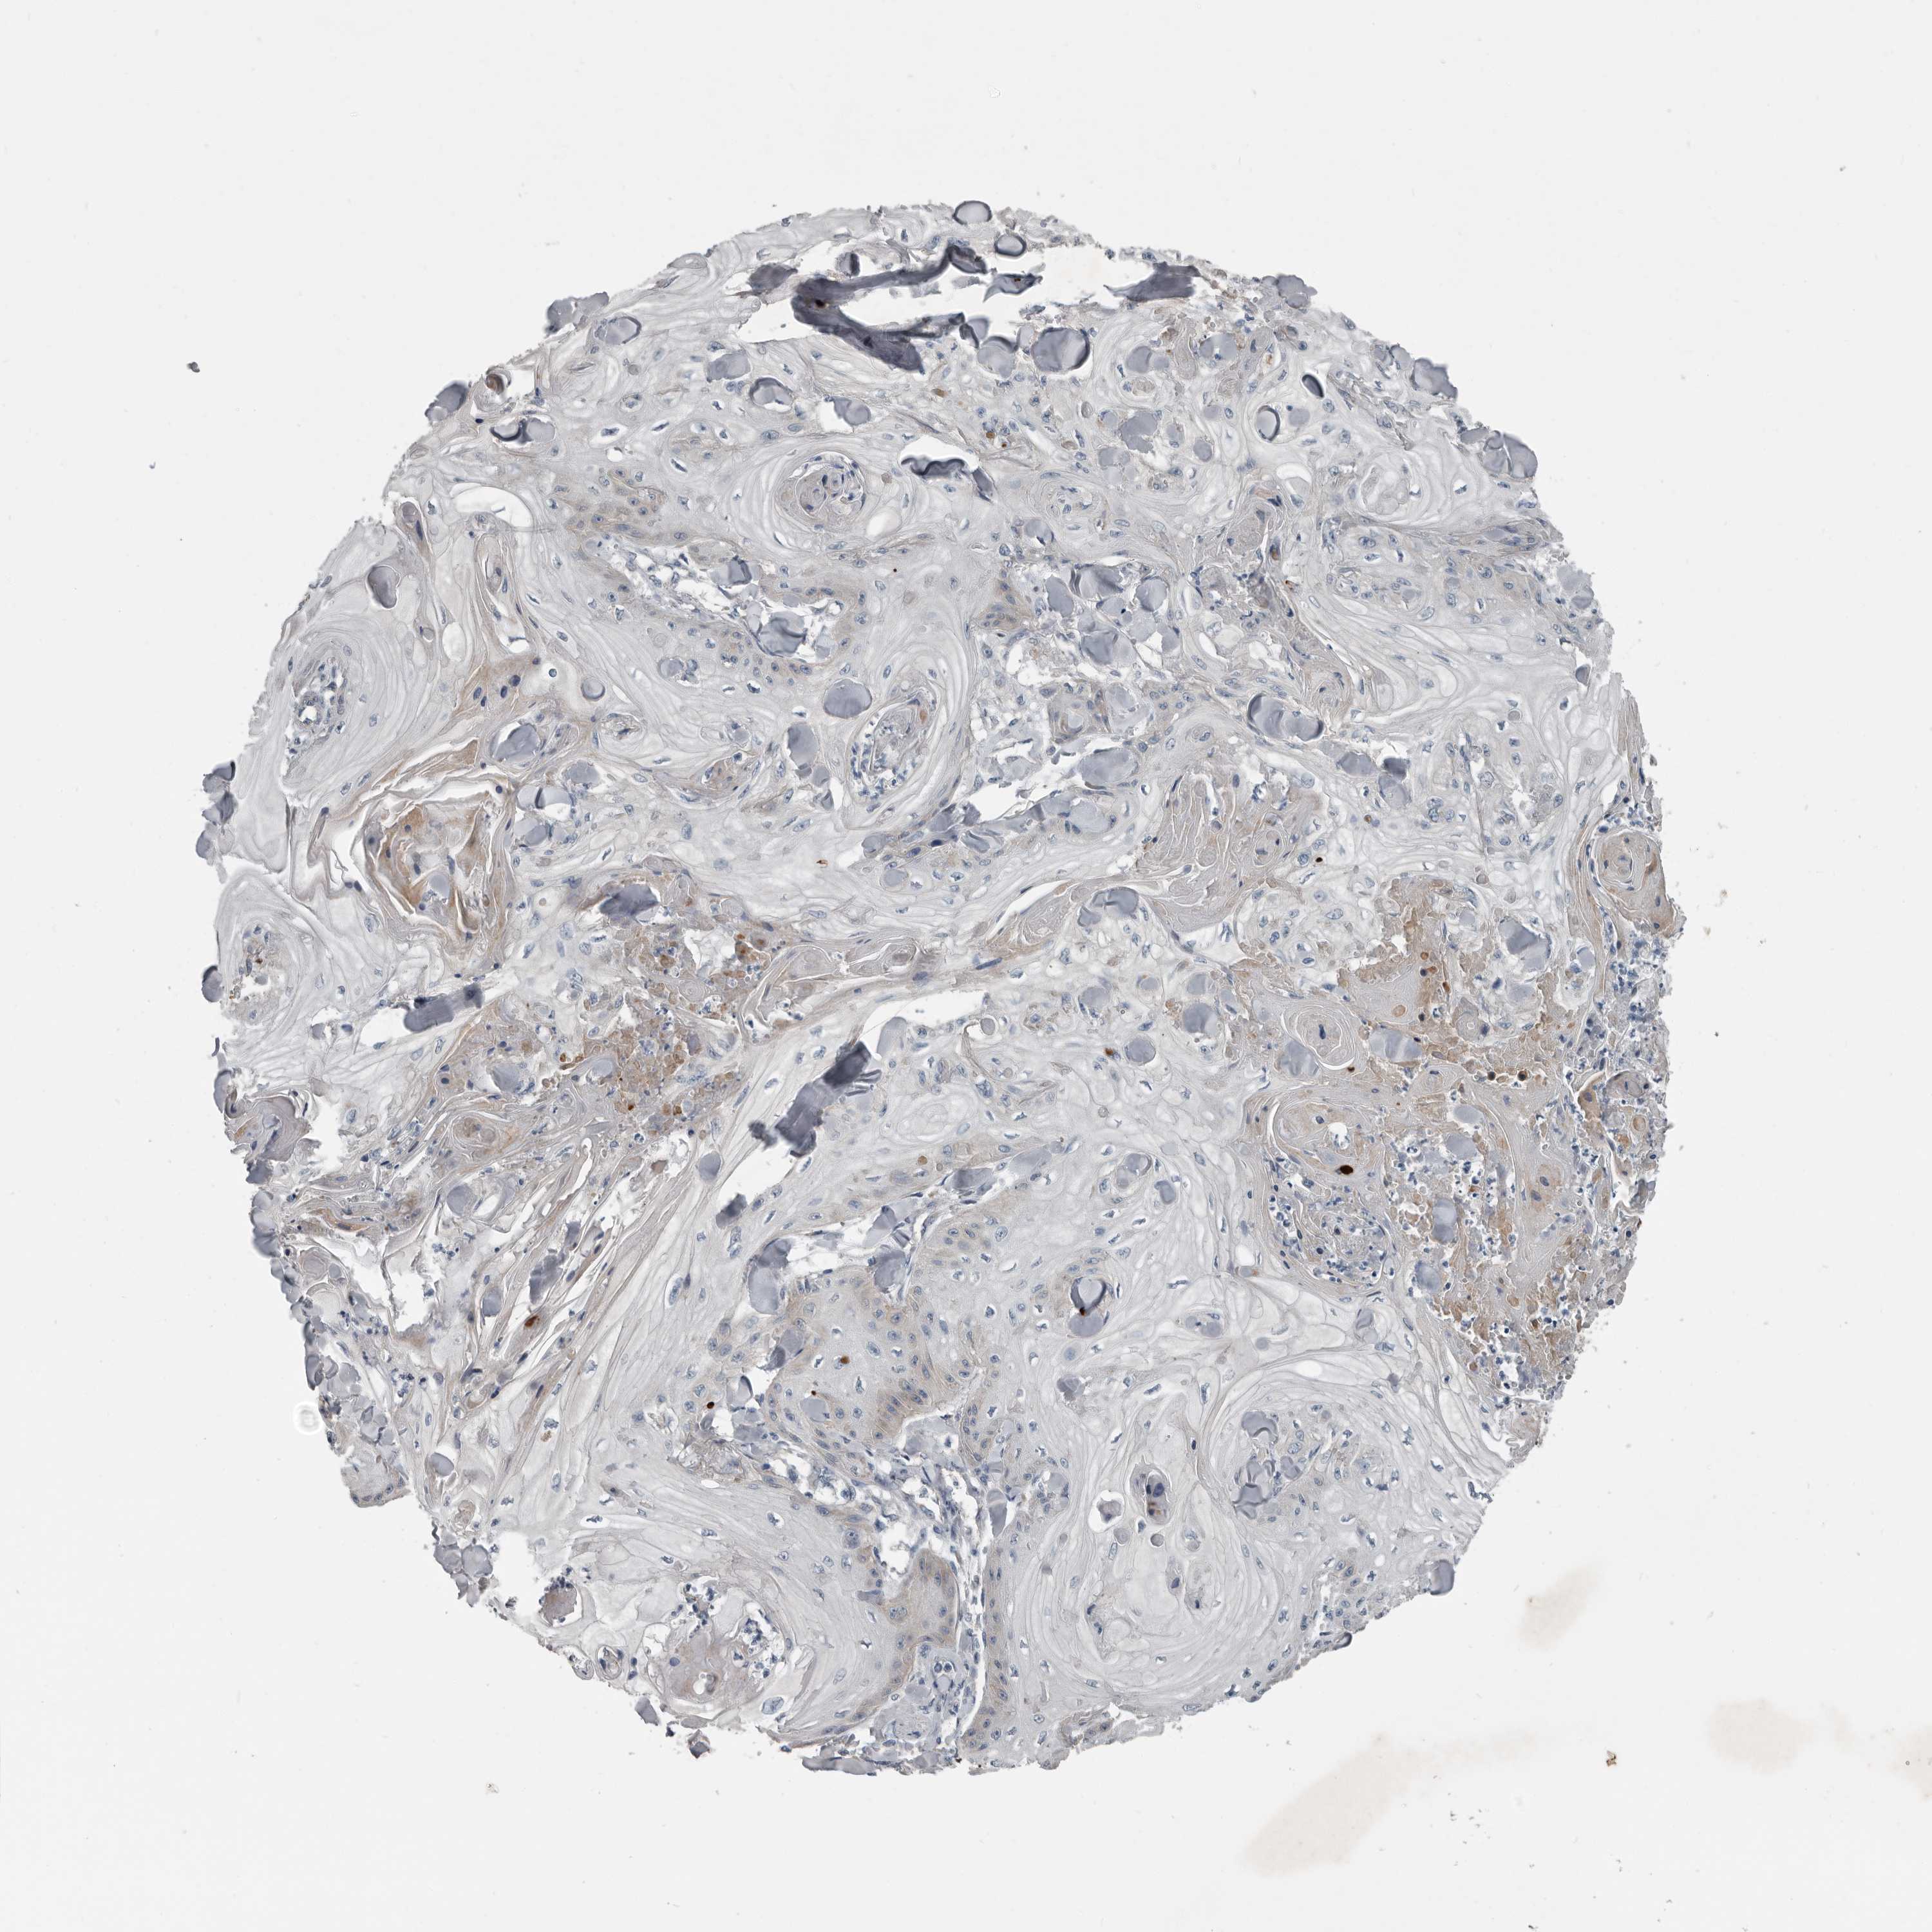

CANCER SKIN CANCER Show tissue menu

Basal cell and squamous cell cancer

SKIN CANCER - Protein expressioni

A mouse-over function shows sample information and annotation data. Click on an image to view it in a full screen mode. Samples can be filtered based on level of antibody staining by selecting one or several of the following categories: high, medium, low and not detected. The assay and annotation is described here.

Each image is clickable and will lead to virtual microscopy that enables deeper exploration of all samples and also displays staining intensity scores, fraction scores and subcellular localization as well as patient and tissue information for each sample.

Antibody HPA024780

Basal cell carcinoma

Squamous cell carcinoma, NOS

Squamous cell carcinoma, metastatic, NOS